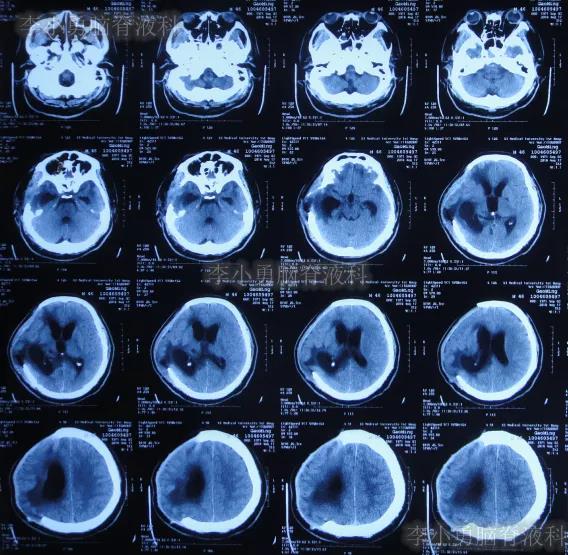

颅骨修补术后35天即2019年5月7日(第4家医院治疗227天即脑室腹壁外引流术后211天)),查头颅CT仍脑室扩张(图-5),且引流出的脑脊液有絮状物。

图-5:2019年5月7日头颅CT

第4家医院治疗257天(8个半月),治疗期间患者曾发作癫痫数次,给予药物控制,引流管也曾更换,虽无发热但意识改善不明显,2019年6月6日查头颅CT示脑室仍大(图-6)。

图-6:2019年6月6日头颅CT

第4家医院治疗312天(10个月),意识仍无明显改善,查头颅CT(图-7)后仍脑室扩张,患者出院转回当地的新疆鄯善县某医院。

图-7:2019年7月31日头颅CT